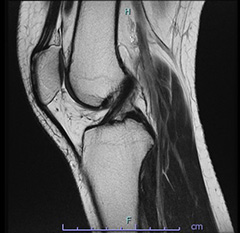

• 画像:損傷後内側半月板MRI画像(側面)

損傷後内側半月板MRI画像(側面)

• 画像:損傷後内側半月板MRI画像(正面)

損傷後内側半月板MRI画像(正面)